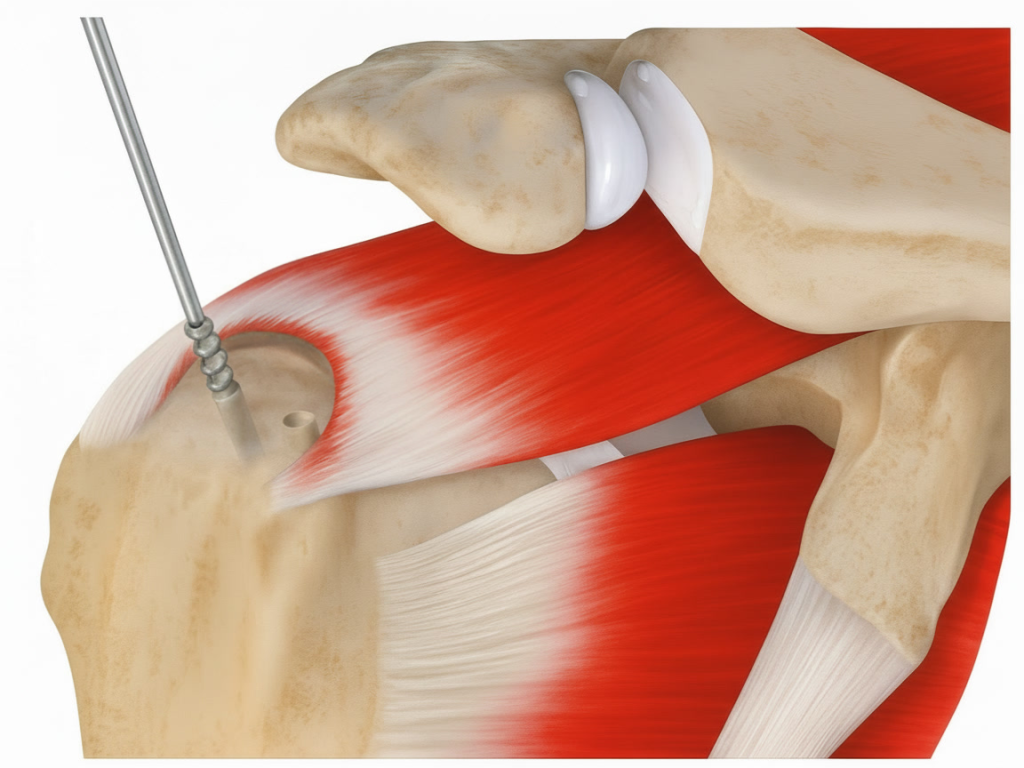

Rotatorenmanschette | Orthopäde 1010 Wien | Dr. Ewald Timmel

rotatorenmanschette von dr. timmel von ortho-timmel.at

Darstellung und Mobilisierung der Sehnenstümpfe

• Débridement von degeneriertem Gewebe.

• Mobilisierung der rupturierten Sehne (meist Supraspinatus, ggf. Infraspinatus/Subscapularis).

• Darstellung des Ansatzbereichs am Knochen (Tuberculum majus/minus humeri).

• Glättung und Anfrischen des Footprints (Sehnenansatzstelle) zur Förderung der Knochen-Sehnen-Heilung.

Naht und Refixation

• Verwendung von Fadenankern (Suture Anchors), die im Humeruskopf eingebracht werden. Die Sehne wird mit Fäden durchstochen und zur Knochenoberfläche zurückgeführt.

• Single-Row-Technik: Eine Reihe von Ankern entlang des Footprints.

• Double-Row-Technik: Zwei Reihen für breitere Kontaktfläche (höhere Stabilität).

• Suture-Bridge-Technik: Verbindung beider Reihen

subakromiale dekompression von dr. timmel von ortho-timmel.at